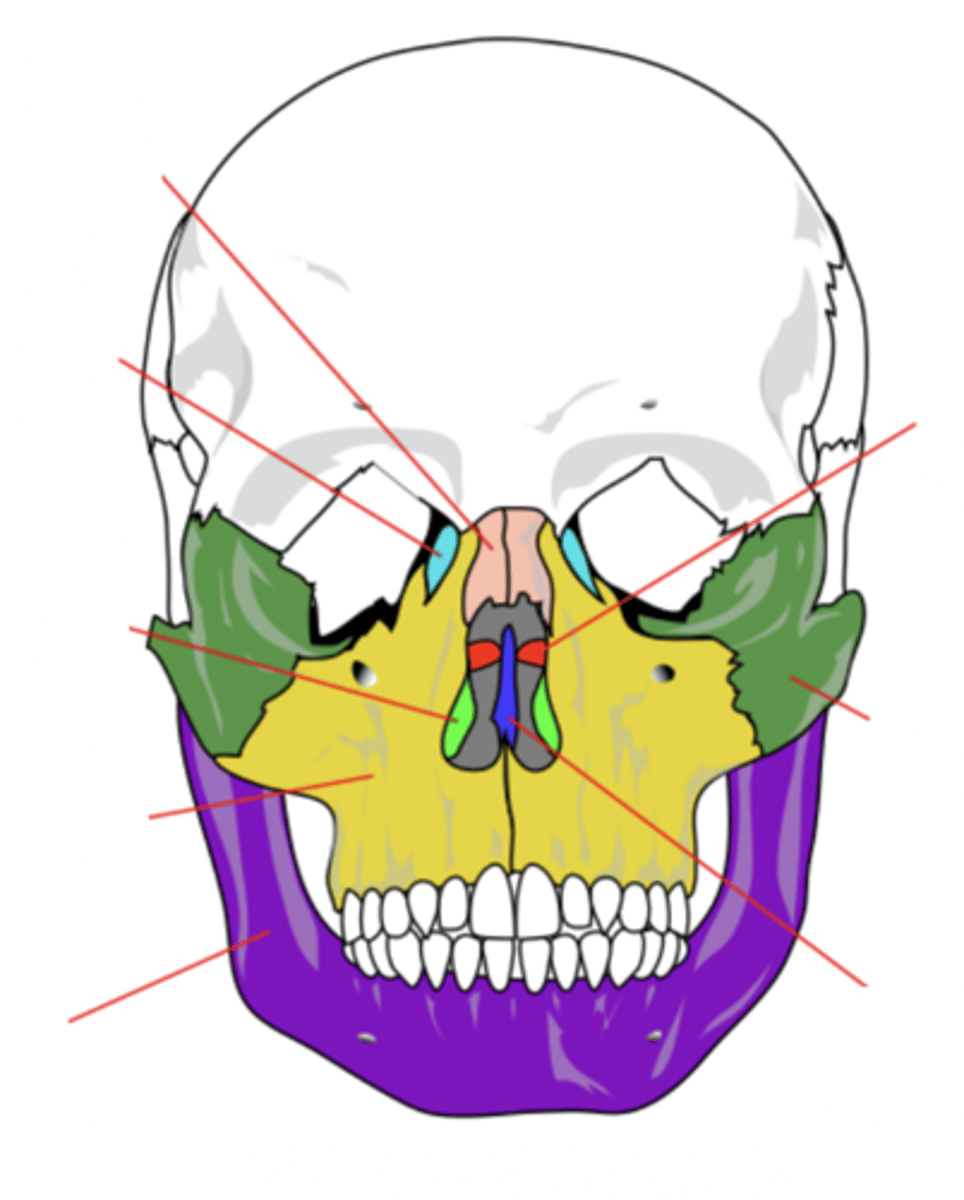

Facial Bones (14)

- Maxilla (2)

- Mandible

- Lacrimal (2)

- Palatine (2)

- Inferior conchae (2)

- Vomer

- Nasal (2)

- Zygomatic (2)

(Many Mammals Like Playing In Very Nice Zoos)

Maxilla Bone (2)

Upper jaw bone (yellow)

Mandible Bone

Lower jaw bone (purple)

Lacrimal Bone (2)

Small fragile bone making up part of the front inner walls of each eye socket and providing room for the passage of the lacrimal ducts (light blue)

Palatine Bone (2)

Bone that forms the hard palate and parts of the nose and orbits (red)

Inferior Conchae Bone (2)

The thin, scroll-like bones that form part of the interior of the nose (light green)

Vomer Bone

Bone that forms the inferior portion of the nasal septum (blue)

Nasal Bone (2)

Bone that forms the bridge of the nose (pink)

Zygomatic Bone (2)

Cheek bone (green)